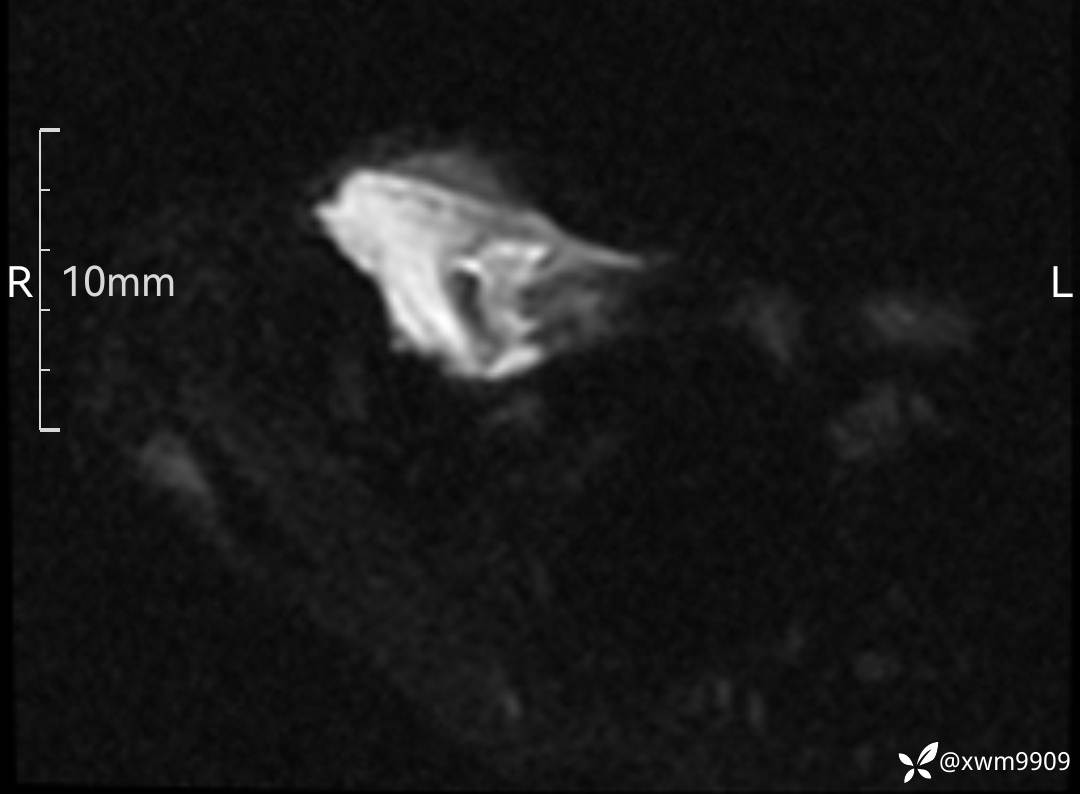

CT:

2、CT、MR肿块内可见液-液平面,常见有哪些疾病。

3、如何定性、定病?